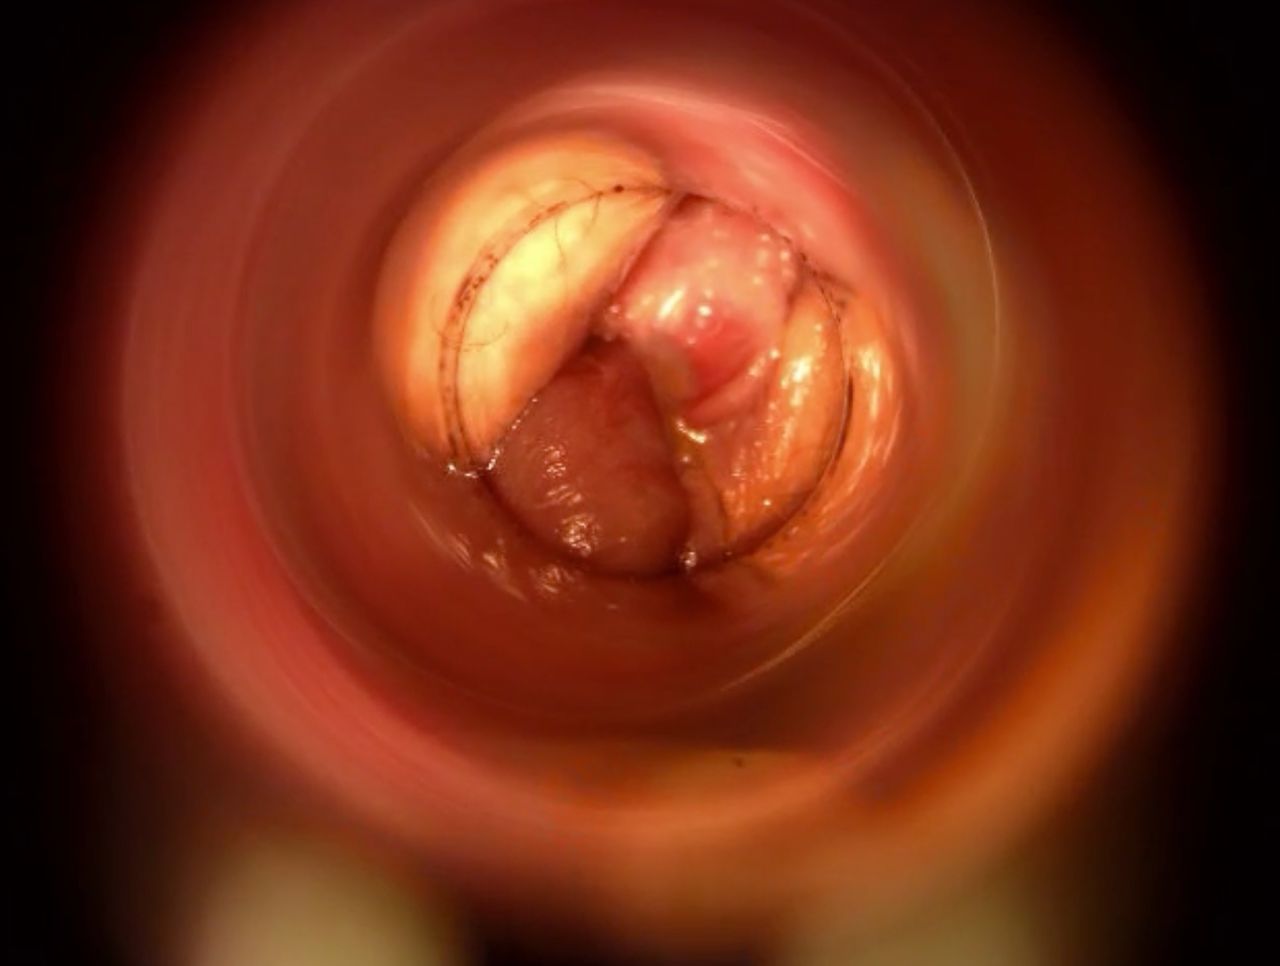

Come Chirurgo Vascolare, sono perfezionata in Proctologia da molti anni, e molti altri ne ho passati direttamente in sala operatoria, praticando l'emorroidectomia con metodo Milligan-Morgan.

Durante la mia esperienza come Chirurgo Protcologo, ho visto personalmente come i trattamenti chirurgici disponibili, benché necessari, fossero comunque abbastanza invasivi per il paziente, specialmente nel decorso post operatorio.

Fortunatamente, negli ultimi anni sono stati messi a punto protocolli non chirurgici molto avanzati, che ho personalmente studiato ed approfondito con molto interesse.

Tra questi, ho cominciato ad utilizzare il trattamento sclerotizzante con scleromousse stabilizzata ad aria sterilizzata, che considero ormai il 'Gold Standard' per il trattamento non invasivo e permanente delle emorroidi patologiche.

Ho quindi attrezzato il mio studio con il moderno Videoproctoscopio Digitale, nonché con avanzate pompe miscelatrici ad aria sterilizzata, in grado di ottenere una scleromousse stabilizzata di grande qualità, perfetta per il trattamento emorroidale.

Grazie a questo protocollo, posso risolvere casi anche molto gravi di prolasso emorroidale, garantendo una risoluzione definitiva in oltre il 95% dei casi clinici.

Il tutto, senza il minimo dolore o disagio per il paziente.